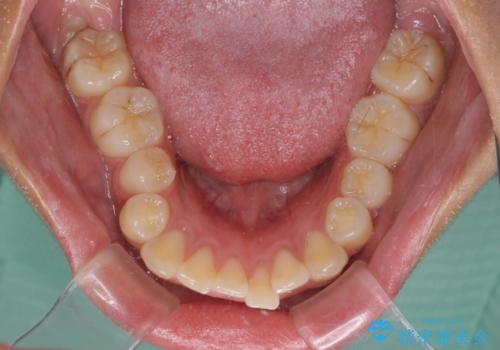

- 出っ歯と口の閉じにくさ、デコボコを気にして来院された患者様です。

舌の突出癖により上下前歯は非接触であり、非常に前方に飛び出している状態でした。

舌のトレーニングをしっかりと行っていただき、口の閉じやすい歯並びに仕上げることができました。